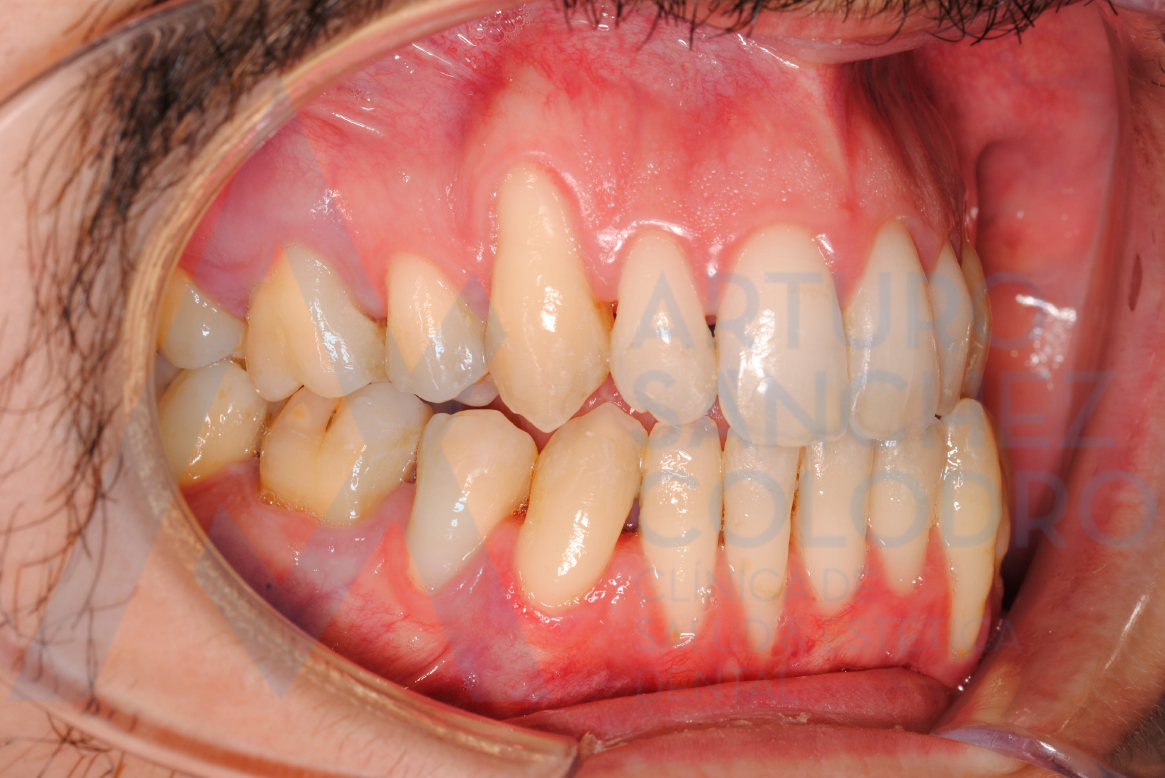

Tras la cirugía mucogingival realizada por el Dr. Arturo Sánchez Colodro en la primera parte de la boca (paciente aún en fase de tratamiento):